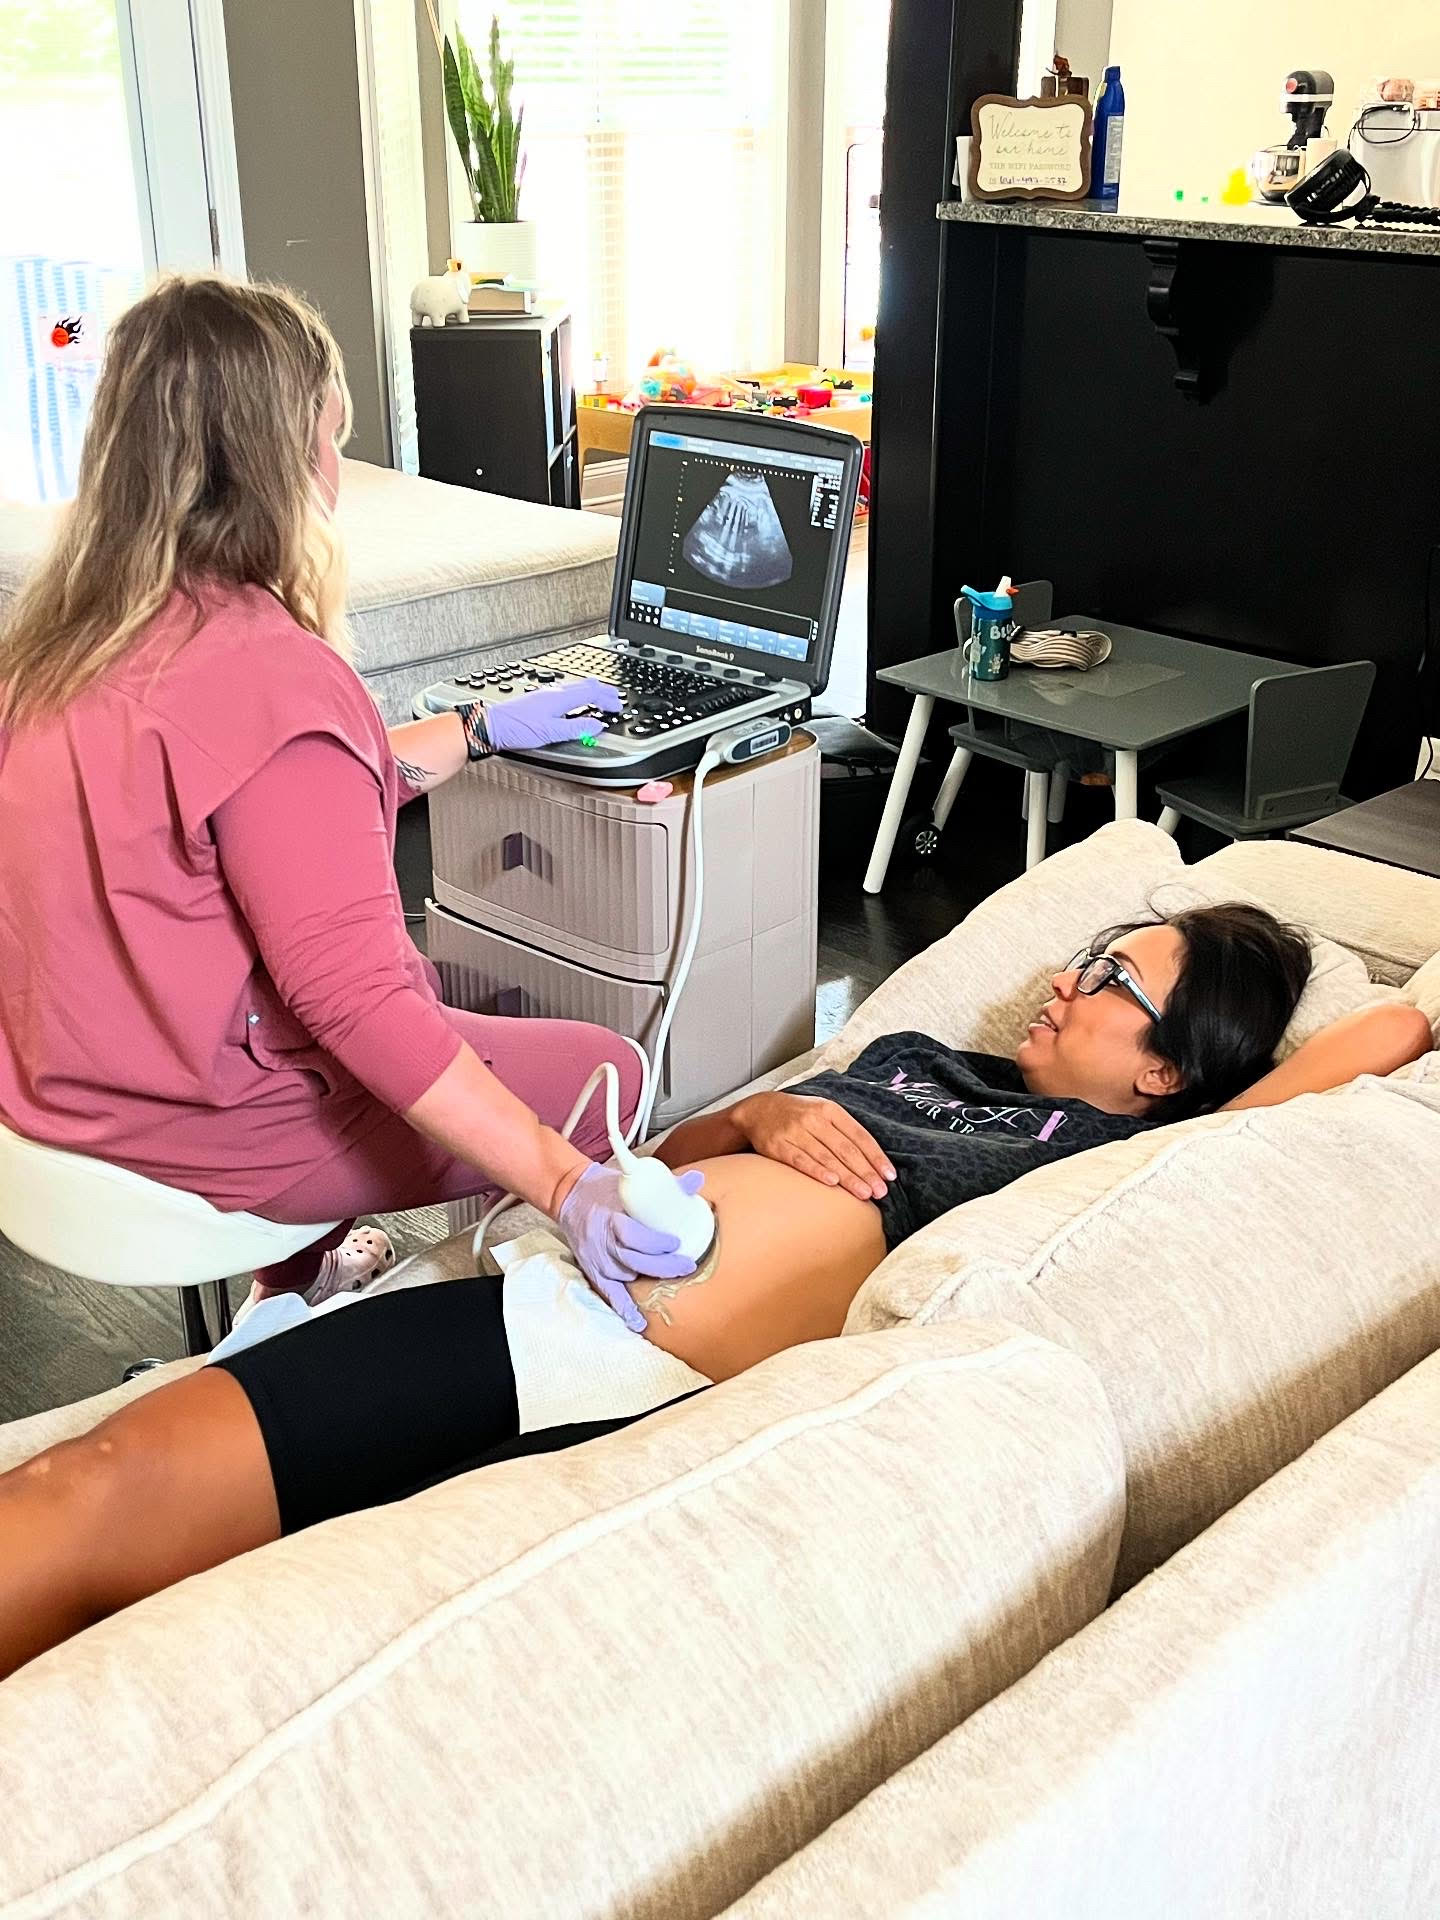

At New Life Imaging, we’re passionate about creating memorable and heartwarming experiences for expectant mothers through personalized, mobile, in-home 3D/4D ultrasounds. Proudly serving Middle Tennessee, including Nashville, Clarksville, and surrounding communities, we strive to nurture the bond between mamas and their babies, all within the comfort and intimacy of their own homes.

Our elective, non-diagnostic ultrasound services offer expectant families the incredible opportunity to witness the beauty of their baby’s first movements, smiles, and tiny features in amazing detail. Each session is designed to be a joyful, stress-free occasion, enhanced by our thoughtful touches like optional heartbeat-stuffed animals, printed Polaroid keepsakes, and digital images delivered straight to your inbox.

Whether you’re celebrating the joyful anticipation of a new arrival or needing heartfelt comfort during a challenging time, New Life Imaging is there. Serving Middle Tennessee, we bring professionalism, compassion, and a deeply personal touch directly to your doorstep. Your family’s journey is precious, and we’re privileged to walk alongside you if you’ll have us.